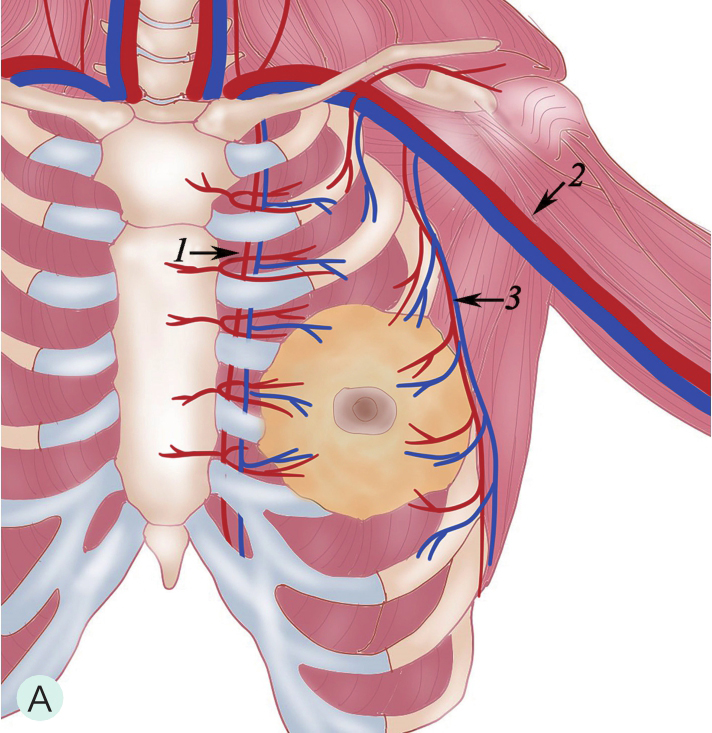

乳腺主要由胸廓内动脉、胸外侧动脉及肋间穿支动脉供血(图1-4-1A~图1-4-1C)。胸廓内动脉发自锁骨下动脉,在相应肋间胸骨旁发出分支穿过胸大肌,主要供应乳房的内侧部分血供;胸外侧动脉发自腋动脉第2段,穿过腋静脉深面,经腋窝沿胸小肌下缘走行,负责胸大肌、胸小肌、前锯肌及乳房外侧部分血供;另外,第3~5肋间动脉从各相应的肋间穿出,与胸外侧动脉及胸廓内动脉分支吻合,供应乳房下部分血供。上述三组主要动脉在乳房内又不断分支并相互吻合形成血管网,且走行自然连续,但缺乏类似于肝脏及肾脏有规律的血管分支树结构,同一女性双侧乳房或不同女性间都不相同,无固定分支规律可循(图1-4-1D)。

图1-4-1 乳腺血供与影像学

A.乳腺血供示意图;B.乳腺增强MRI造影血管图;C.乳腺增强MRI三维重建血管图;D.乳腺血管铸型解剖标本

1.胸廓内动脉;2.腋动脉;3.胸外侧动脉